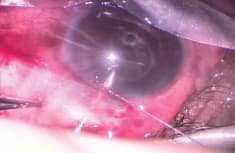

A clear corneal traction suture can expose the conjunctival quadrant of interest. A fornix or limbal-based peritomy at the 4 to 5 o’clock position enables blunt dissection posteriorly. For valved implants, one should prime the device with balanced salt solution on a 30-gauge cannula to ensure the valve is functioning and the system has adequate flow. The implant is placed 9-10 mm from the limbus and sutured to the sclera with 8-0 or 9-0 sutures on a spatulated needle (Figure 1). The tube is then trimmed to the proper length.

Figure 1. Fixation of the Baerveldt Glaucoma Implant plate to the sclera is accomplished with 9-0 nonabsorbable suture passed through the implant eyelet.